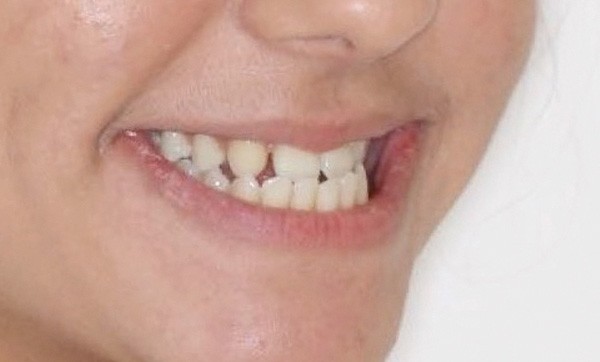

La jeune patiente présente, à l’examen clinique extra-oral, une tendance classe III qui se traduit par une protrusion de la lèvre inférieure de profil, et un menton très présent lors du sourire (fig. 1). À l’examen intra-oral, l’arcade maxillaire est en V, les incisives latérales permanentes droite (12) et gauche (22) sont manquantes et les espaces presque refermés. À l’arcade mandibulaire, un léger encombrement incisif est présent. En occlusion, elle présente une classe I molaire et canine et une occlusion inversée antérieure qui se prolonge à droite sur la première prémolaire (14) (fig. 2 à 5).